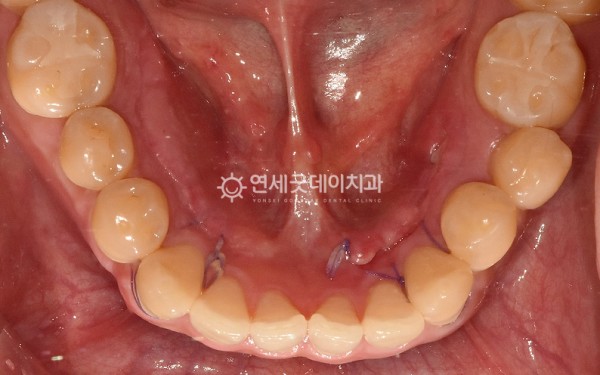

하악골융기가 신경쓰이고

불편하다는 주소로

내원해주신 30대 남성분이십니다.

환자분은 하악골융기 하방으로

음식물이 많이 끼고 신경쓰이는 듯한

불편함을 호소하셨으며

혀 밑으로 양쪽에 크기가 큰 토러스가 관찰되었습니다.

하악골융기 제거 직후로,

울퉁불퉁한 골융기가 제거되고

잘 아물수 있도록 깔끔히 봉합해드렸으며

10일 후 경과체크를 위해 내원하셨을 땐

토러스 제거부위가 잘 아물고 있었습니다.